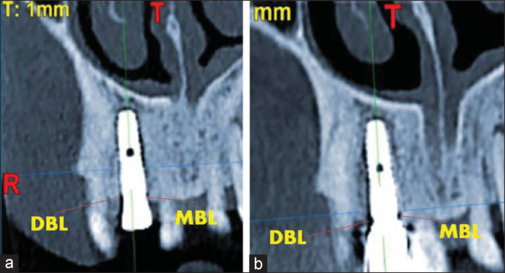

Materials and methods: Thirty subjects were randomly divided into two groups: group A or PRF group and group B or non-PRF group with fifteen patients in each group. Clinical parameters such as implant mobility and bleeding on probing were recorded. The radiographic parameters such as bone density in Hounsfield units (HU) and marginal bone loss (mm) were measured using cone-beam computed tomography (CBCT).

Results: No significant difference in the mean marginal bone level scores between PRF group and non-PRF group (intergroup) at baseline and at 3 months was observed. A Statistically significant difference was observed in the mean bone density (HU) in the PRF group (intragroup) between baseline and 3 months and also in bleeding on probing between baseline and 6 months in the PRF group (intragroup).